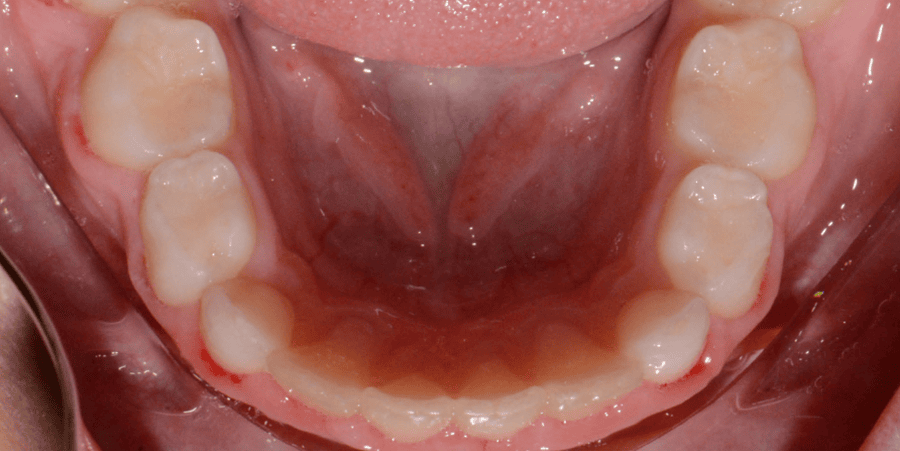

After